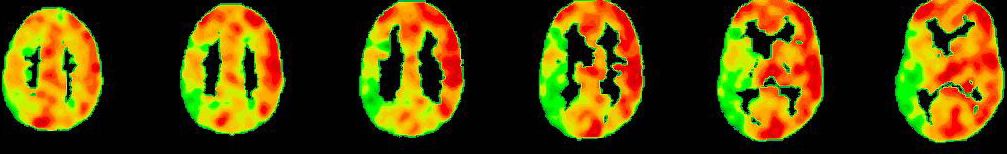

PET-CT nach Diamox Gabe

PET-CT nach Diamox Gabe zeigt eine einseitig deutlich reduzierte Perfusionsreserve (grüne Farben) im Vergleich zur Gegenseite mit ausreichendem Anstieg der Durchblutung (warme Farben).